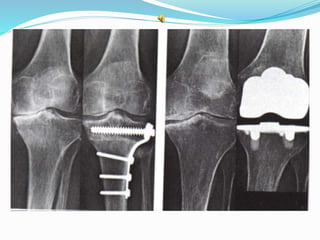

INDICATIONS OF SURGICAL

INVASIVE METHODS

 Surgery

Osteotomy

Joint replacement

INDICATIONS OF SURGICAL INTERVENTION Severe joint pain, resistant to conservative treatment methods  Limitation of daily living activities  Deformity, angular deviations, instability

INVASIVE METHODS  Jointlavage  Arthroscopy  Cartilage grefting- genetic engineering  Surgery Osteotomy Joint replacement